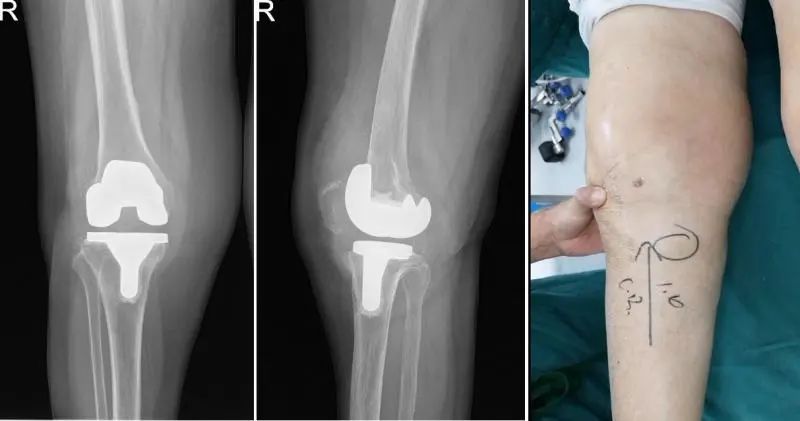

Spacer植入术后平片显示Spacer假体位置良好

Spacer植入术后患者膝关节屈伸活动度良好